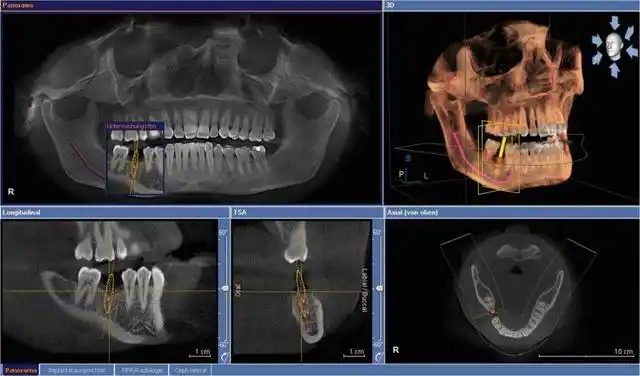

口腔全景片(曲面断层片)是口腔科检查中十分重要的常规检查手段,主要

口腔全景片提供的是二维影像,所以它的分辨率不如ct高,而且只能提供一

伯爵cbct影像篇③口腔全景片认知